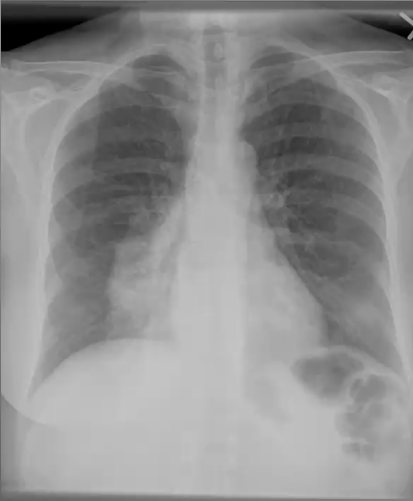

What’s your diagnosis?

Left lingula pneumonia because loss of left heart border (silouhette sign)